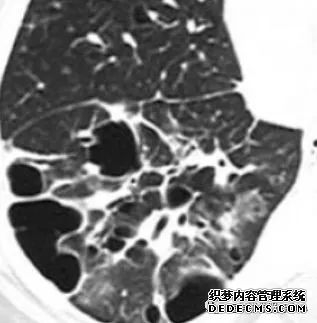

肺转移瘤的十种不典型CT表现